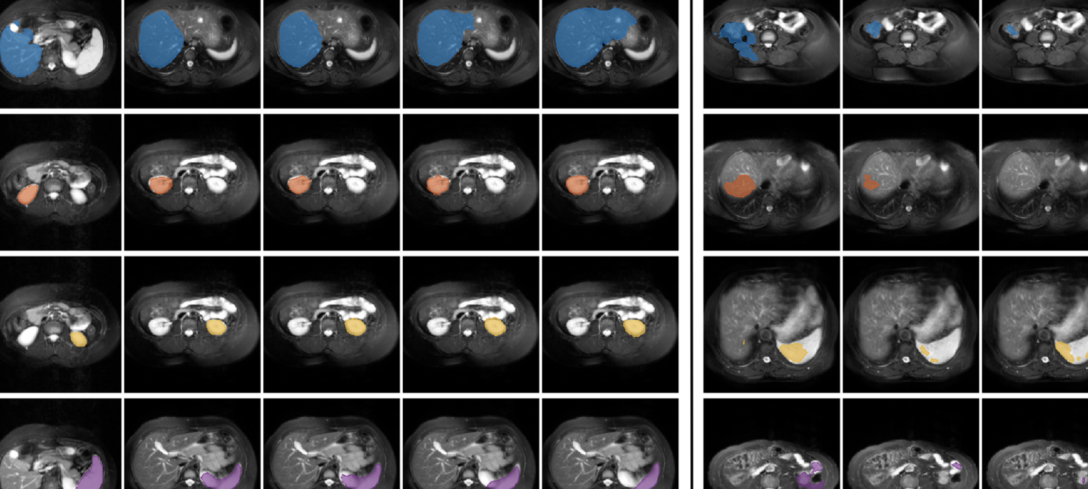

Refer to caption

Fig. 5: Qualitative comparisons for the abdominal MRI dataset. To the left of the solid line, we see (left to right) the support image, the segmentation results of a query slice containing the foreground class, and the ground truth segmentation of this query image. To the right, we see segmentation results for query slices not containing the foreground class. Top to bottom: liver, right kidney, left kidney, and spleen. The proposed method is more robust to background outside the support slice, resulting in less over-segmentation.

In a more realistic scenario, information about the location of the foreground volume in the query images is typically not available. We therefore evaluate the models under EP2 (Table 2) and we observe that our proposed approach outperforms the state-of-the-art. One-sided Wilcoxon signed rank tests [54] on the mean dice scores across all runs indicate a significant difference between the segmentation results obtained from vSSL-ADNet and pSSL-ALPNet for both datasets under EP2 (p<0.05𝑝0.05p<0.05). For the abdominal data, our model improves the segmentation results by more than 20 percentage points compared to pSSL-ALPNet. The main reason for this large improvement is that we now have to consider all the query slices (not only the slices containing the organ to be segmented), meaning that the background class is much larger and much more diverse. This again complicates the task of modeling the background with prototypes, whereas our anomaly detection-inspired model without background prototypes is less affected. The somewhat lower performance and high standard deviation for left-kidney and spleen are related to the weak boundaries between these organs (see discussion in Section 6). Furthermore, we obtain considerable, but smaller, improvements on the cardiac dataset under EP2. This is related to the lower number of slices and the less diverse background in these images, making the task of modeling the background with prototypes less complicated. Qualitative comparisons are provided in Fig. 5 and Fig. 6, where we can see that our approach is less prone to over-segmentation.